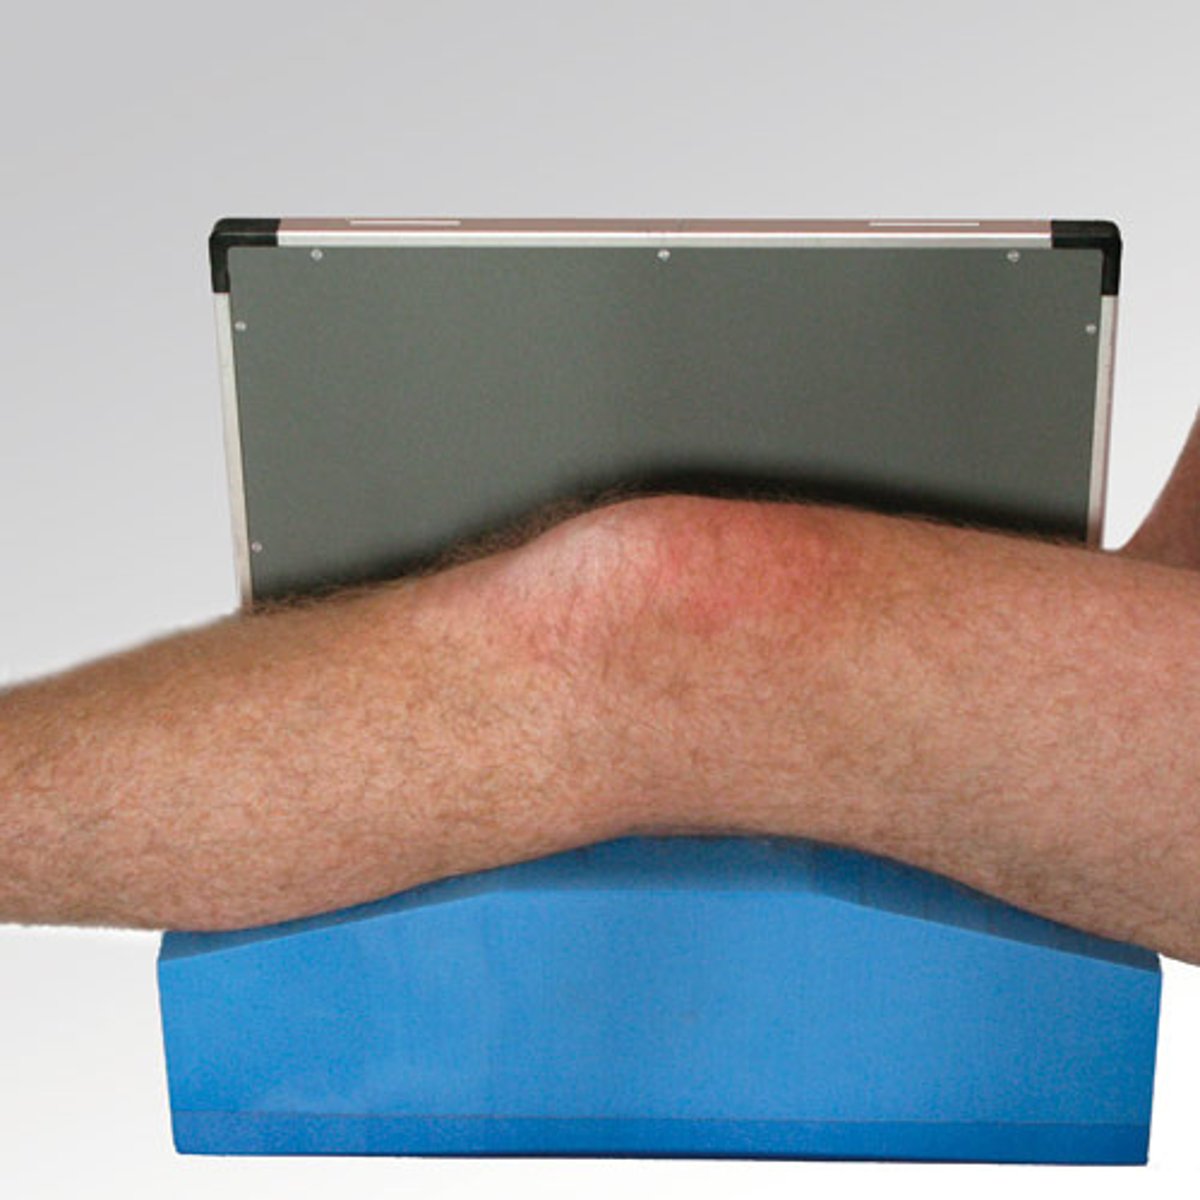

Describe, in detail, the positioning of the PATIENT when doing a supine LATERAL KNEE (non-trauma) (position 1)

1. Patient lies supine on the x-ray couch and turns onto the affected side so that the lateral aspect of the knee is in contact with the IR.

2. The affected knee is flexed through either 45 or 90 degrees and the leg is turned to superimpose the femoral condyles.

3. A small pad should be placed under the ankle joint to ensure the tibia is parallel to the x-ray couch.

Describe, in detail, the positioning of the PATIENT when doing a supine LATERAL KNEE (non-trauma) (position 2)

1. Patient lies on the affected side to be examined and the knee is flexed at either 45 or 90 degrees.

2. The unaffected leg is brought in front of the one being examined.

3. A small pad should be placed under the ankle joint to ensure the tibia is parallel to the x-ray couch.

4. The femoral condyles of the knee being examined should be superimposed.